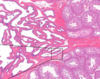

המבנה הבא הוא של איבר במערכת הרביה הזכרית, מהו?

ומה מסומן בחץ מספר 1?

אשך

Tunica Vaginalis

המבנה הבא הוא של איבר במערכת הרביה הזכרית, מהו?

ומה מסומן בחץ מספר 2?

אשך

Rete Testis

המבנה הבא הוא של איבר במערכת הרביה הזכרית, מהו?

ומה מסומן בחץ מספר 3?

אשך

Epididymis

המבנה הבא הוא של איבר במערכת הרביה הזכרית, מהו?

ומה מסומן בחץ מספר 4?

אשך

Seminiferous Tubules

המבנה הבא הוא של איבר במערכת הרביה הזכרית, מהו?

ומה מסומן בחץ מספר 5?

אשך

Tunica Albuginea